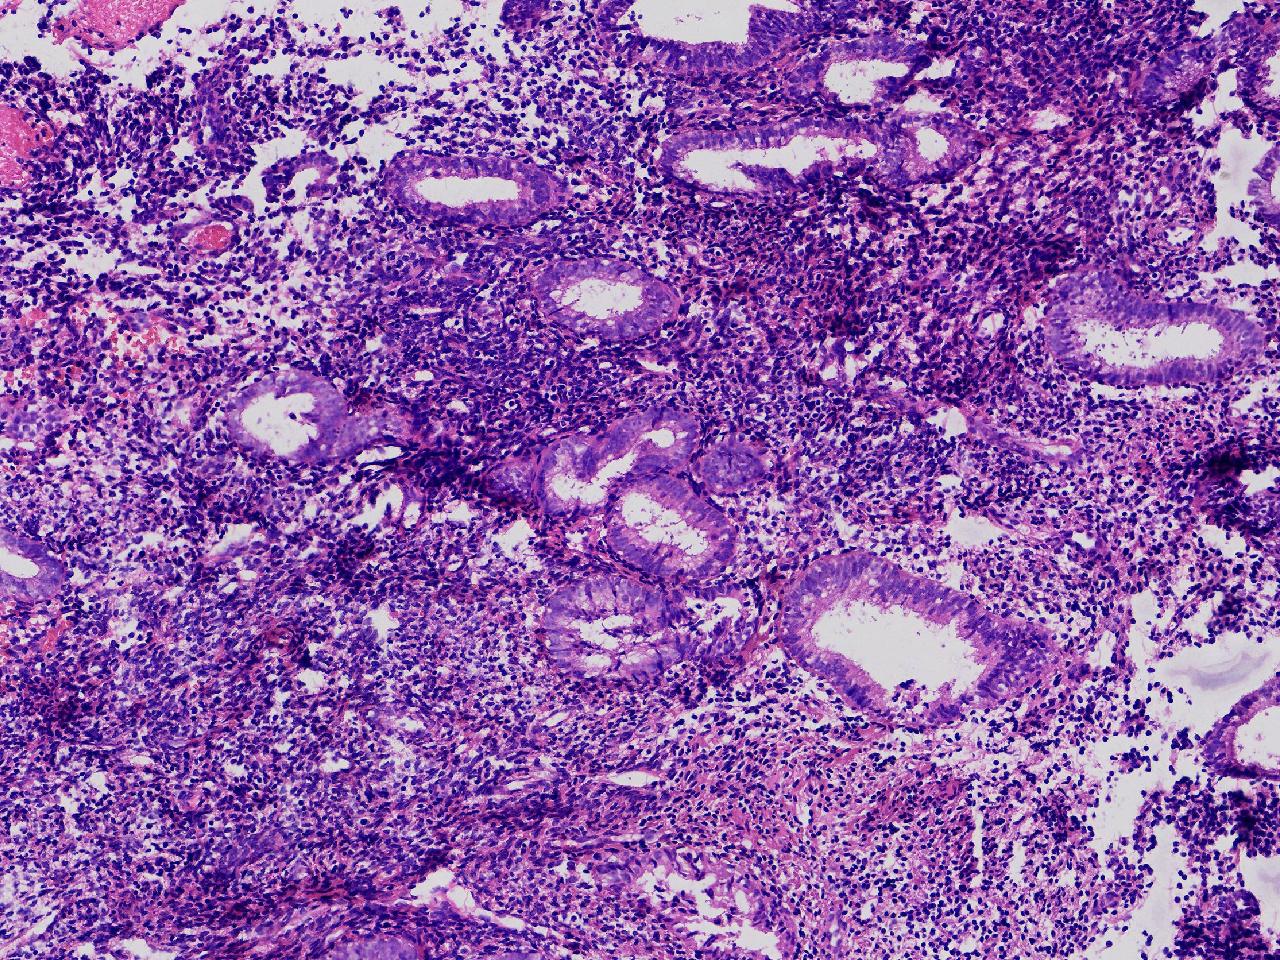

请教诊断。局灶够不够非典?

性别

女

年龄

44岁

阴道不规则出血20余日,彩超示:内膜线居中,厚15毫米。

子宫内膜

灰粉色不整形软组织多块,3X2X1厘米。

不够非典

有输卵管上皮化生,感觉不够非典。